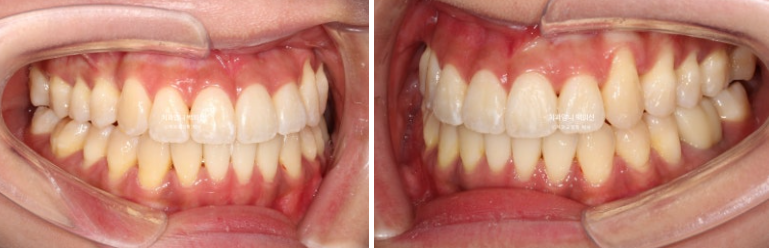

23.09~25.03

초진 3mm의 중심선 불일치가 해결되었습니다.

윗니가 아랫니를 덮는 양이 안정적입니다.

잘 내려와준 덧니입니다.

앞니가 거꾸로 물리던 부분도 정상교합을 찾았습니다